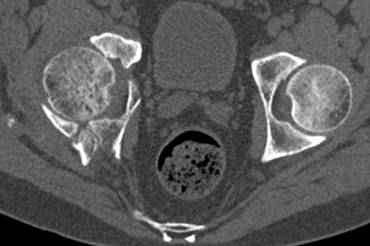

Re: перелом правой половины таза

высылаю дополнительно сканы.